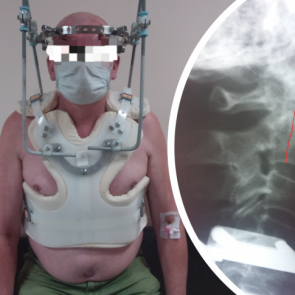

Мужчина упал со стремянки и через 2 недели пришел к врачам с головной болью. С такой травмой люди обычно умирают 0